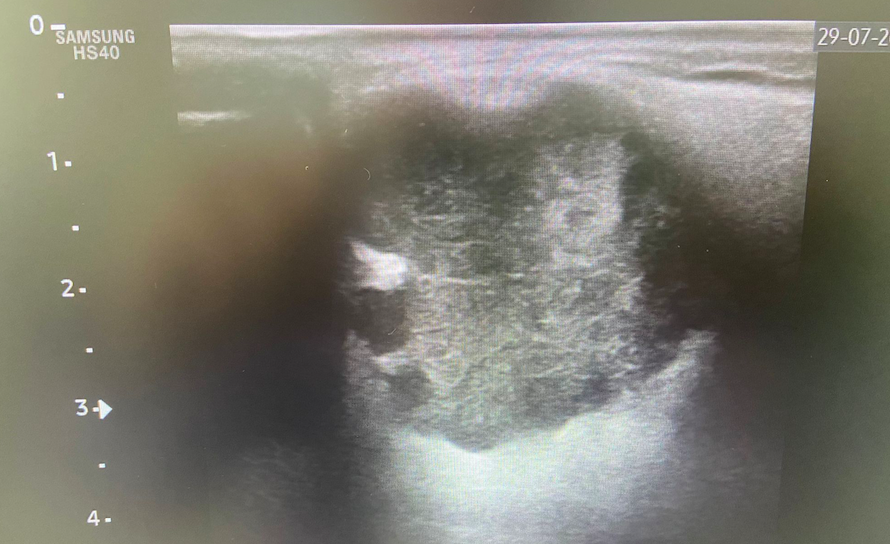

PC: Ecografía clínica en consulta: se identifica en ángulo mandibular izquierdo una lesión nodular bien delimitada, de morfología ovalada, heterogénea, de aproximadamente 28 × 39 mm, con ligera captación Doppler.

Hallazgos ecográficos